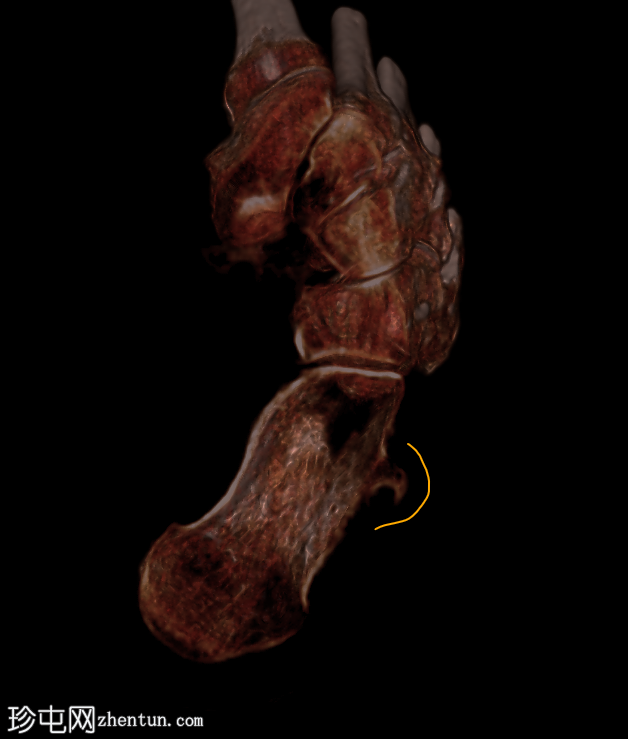

跟骨外侧

疼痛

。

年龄:65岁

性别:女

腓骨结节解剖图(带注释)

病例讨论